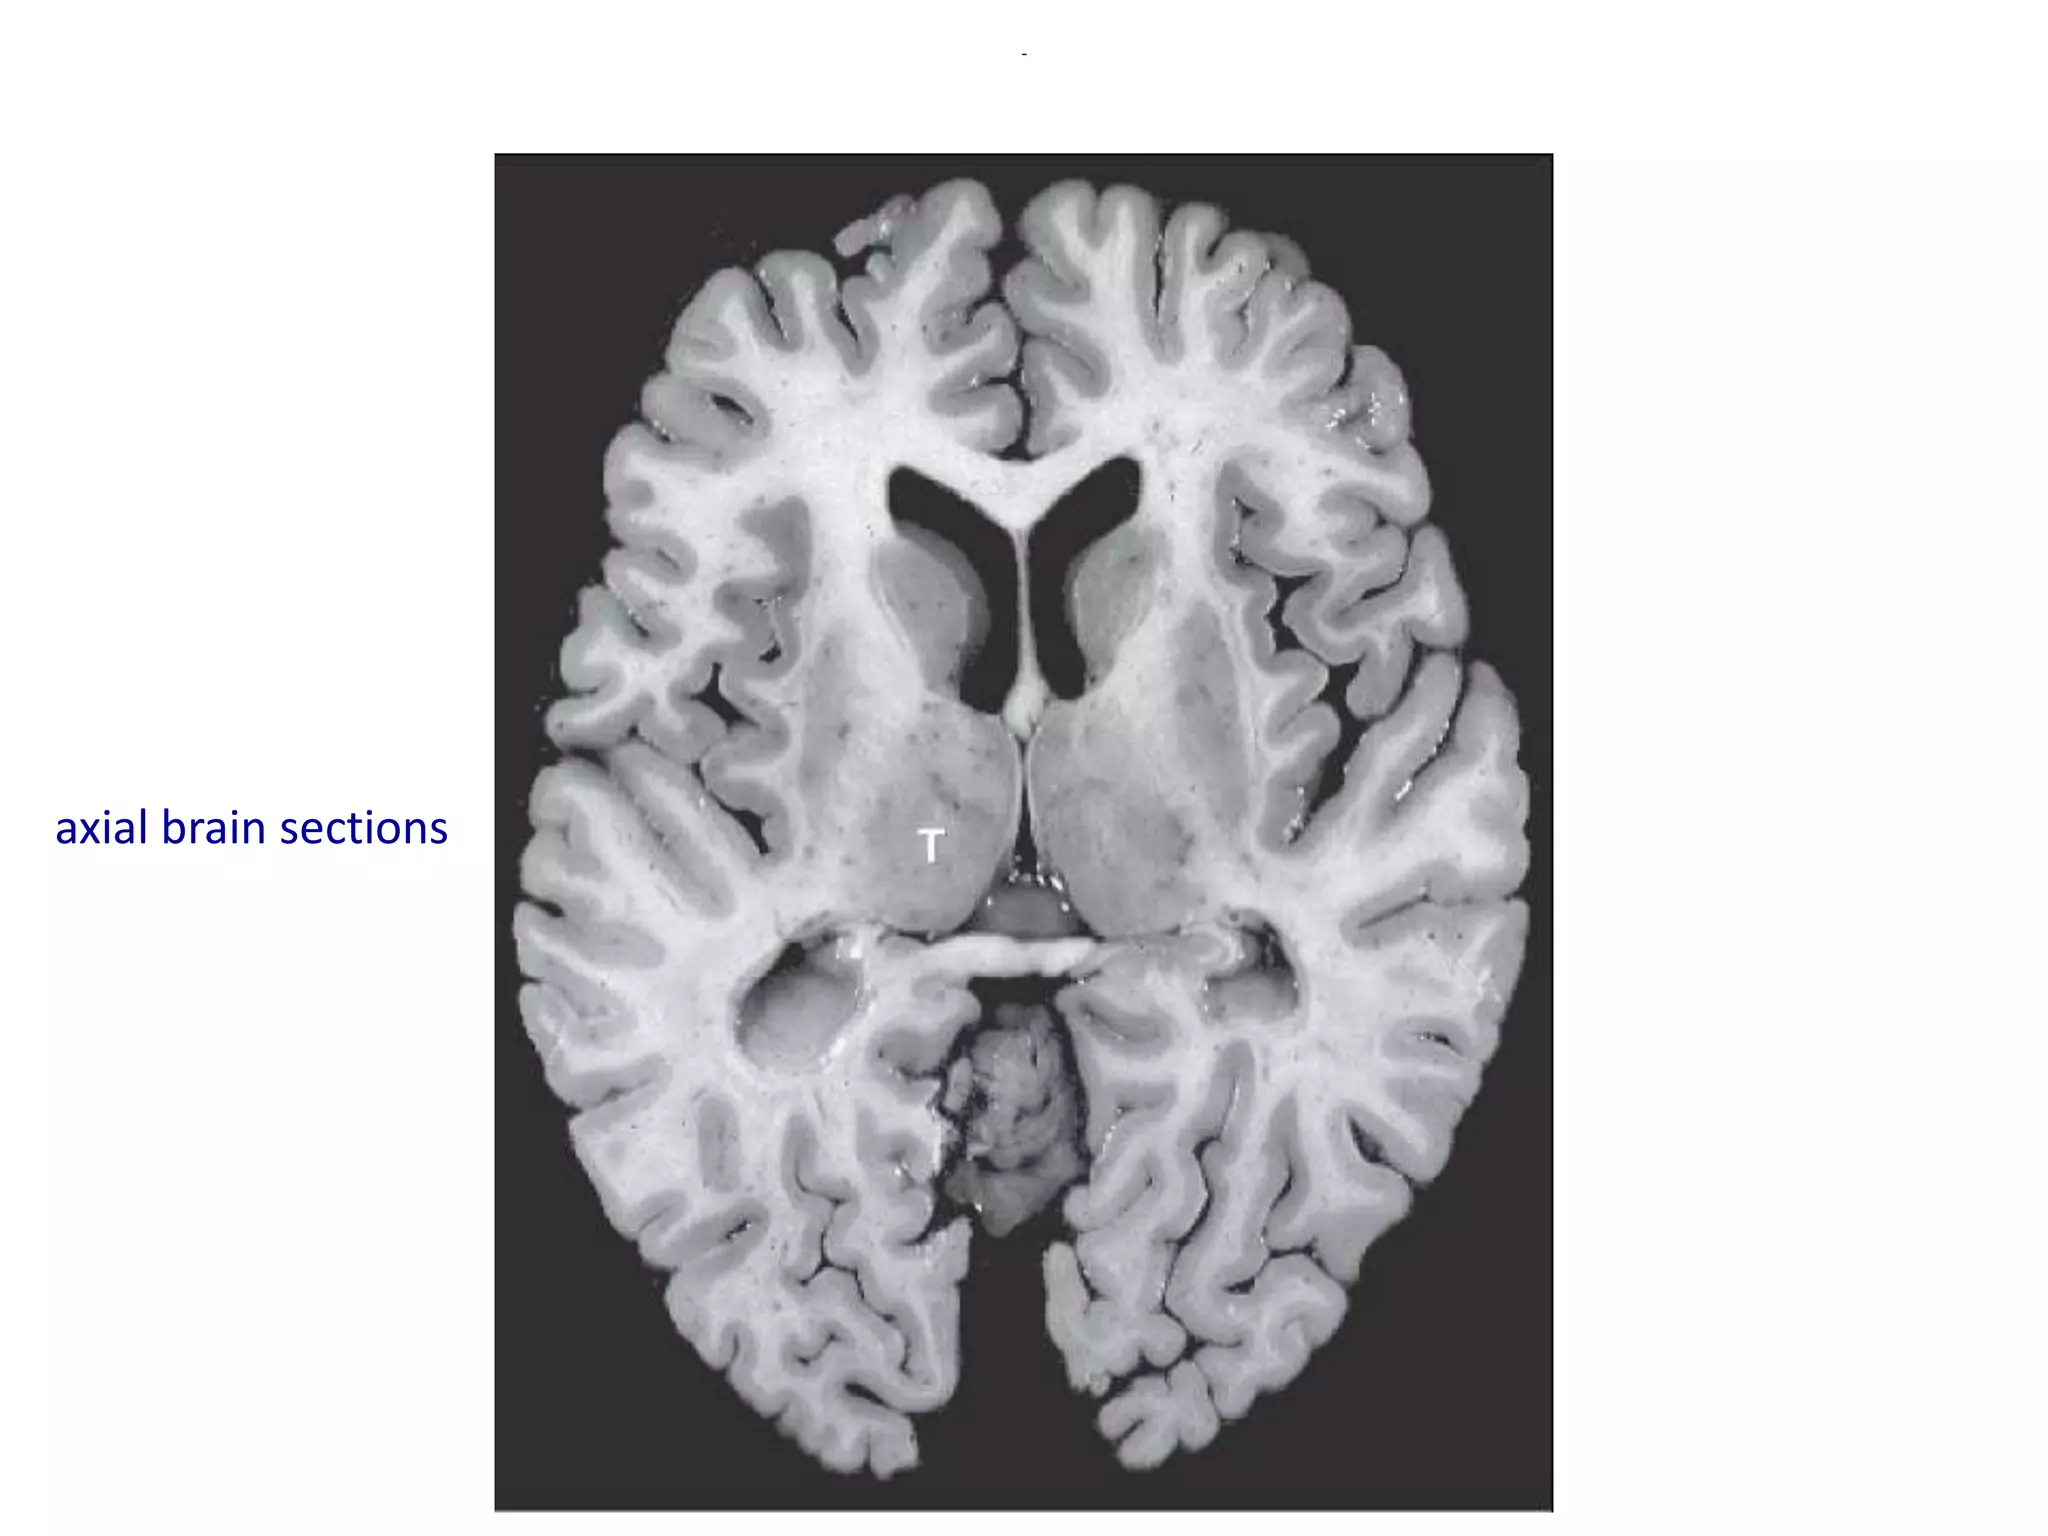

Coronal

axial brain sections

• It is a paired oval mass that surrounds the third

ventricle and lies medial to the posterior limb of

the internal capsule